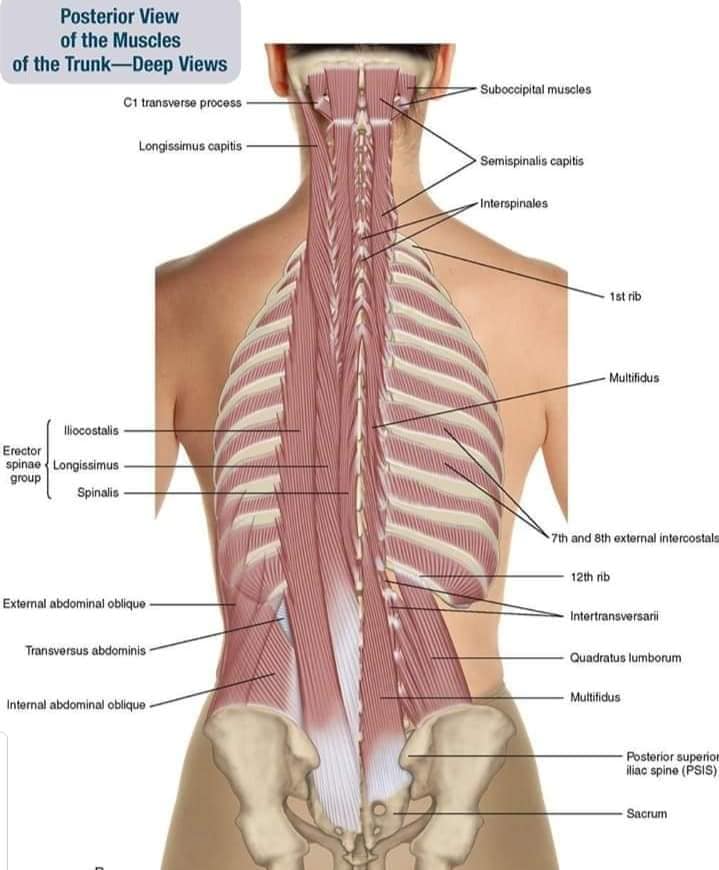

Спинні м'язи

Спинні м'язи виконують функції підтримки хребта, а також дозволяють здійснювати рухи тулуба.

Поверхневі спинні м'язи

М'язи, що піднімають лопатку: Трапецієподібний м'яз: великий м'яз, що покриває верхню частину спини. Його функція - підтримка і рух лопаток, а також забезпечення стабільності хребта.

М'язи, що ведуть лопатку до хребта: Широкий м'яз спини: великий м'яз, що розташований в нижній частині спини. Він відповідає за рухи плечей і лопаток, а також за розширення верхньої частини тулуба.

Глибинні спинні м'язи

М'язи, що забезпечують стабільність хребта: М'язи, що розташовані між хребцями: включають мускулатуру, яка забезпечує стабільність і підтримку хребта, а також дозволяє здійснювати рухи хребта.

М'язи, що здійснюють ротацію та нахили

М'язи, що забезпечують ротацію хребта: Ротаційні м'язи: допомагають у здійсненні обертальних рухів тулуба, а також у підтримці рівноваги і стабільності хребта.